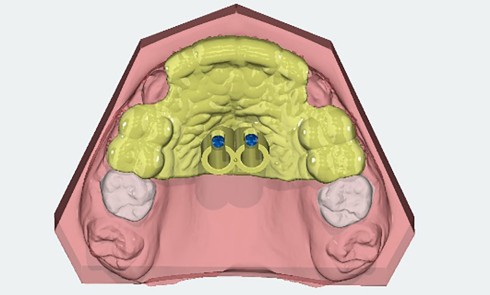

L’impression 3D en orthodontie : faut-il s’équiper ?

Applications en orthodontie [1-3] Champs d’application classiques L’impression 3D ouvre l’accès à un large éventail d’applications orthodontiques, avec notamment l’impression...Dysfonctionnements temporo-mandibulaires : mythes et réalités

La mise en œuvre d’un traitement prothétique implique la collecte de données biologiques (fonctionnelles et esthétiques), afin de créer une...Vidéos